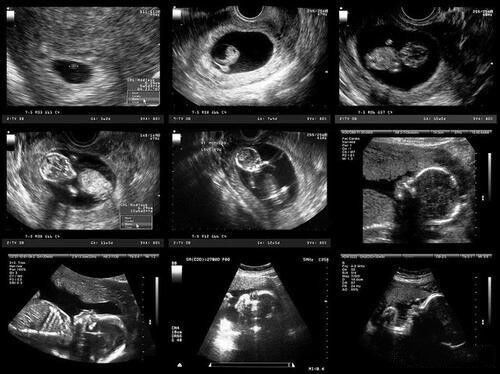

好多人怀孕了总想提前知道宝宝是男是女,不全是因为重男轻女,多数时候就是好奇。想知道b超怎么看男女吗?别急给大家找出了男孩女孩b超的区别,附有图片,一看就懂,轻松识别胎儿性别!

1、看图像

咱们先看B超图上有没有三条线,有的话,基本就是女宝宝啦;如果没有,那就是男宝宝。再来看有没有凸起的部分,像是团状的,那大概率是男宝宝;要是平平的,就是女宝宝。女宝宝两条腿中间能见到三条细线,男宝宝那儿会看到小凸起,也就是睾丸。